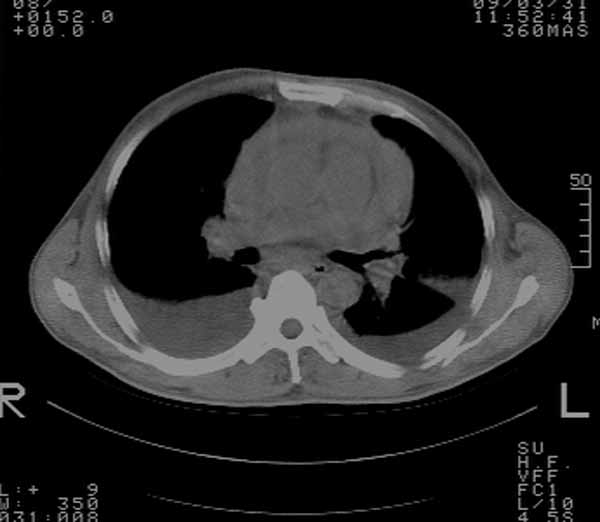

以下是引用余辉在2009-3-31 18:43:00的发言:[br]肺水肿,双侧心腔积液,心包积液,心影增大,疑似心衰

以下是引用wangyong1977在2009-3-31 20:46:00的发言:[br]肺水肿,双侧胸腔积液,心包积液,心影增大,疑似心衰 [br]

以下是引用宇宙ct在2009-3-31 18:57:00的发言:[br]肺水肿,双侧心腔积液,心包积液,心影增大,疑似心衰 [br] [br]